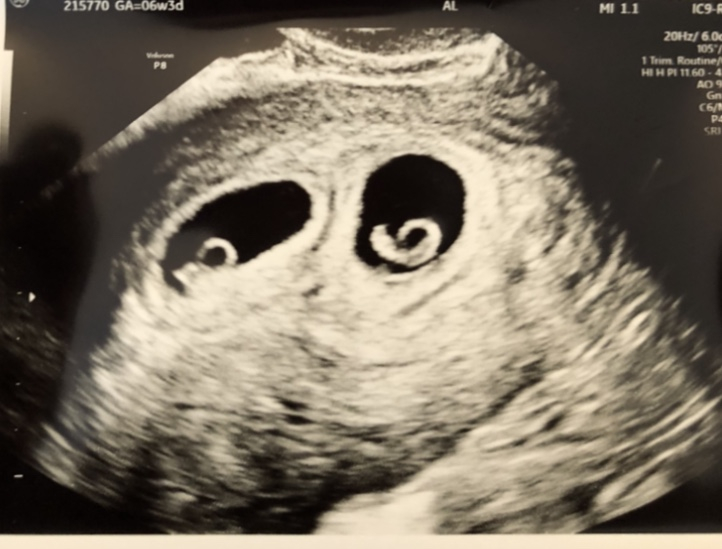

*How far along are you? 6 weeks tomorrow

*Questions, concerns or other? Anything else exciting to share? It was a not very fun exciting weekend over here, I had a small red bleed on Saturday afternoon, we freaked out and called the emergency RE line. It did stop and never filled a pad so we're hoping it was an isolated incident. We both knew that bleeding is really common in IVF pregnancies, but knowing it and seeing it are two very different things! File under things I never thought I would do: giving MH reports about what my tp looked like every time I go to the bathroom

Just going to count the days until my first ultrasound on Friday at this point.

@mvt2003 I've had three small bright red bleeds this pregnancy. It's definitely scary! YAYYYYY for twins!